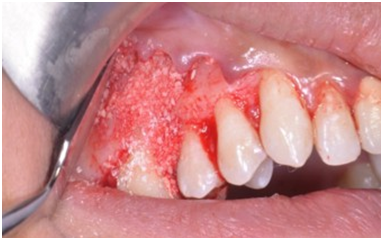

After 4 weeks, surgical intervention was carried out. Under local anesthesia a full thickness mucoperiosteal flap was reflected to entirely expose the underlying bony defect (Figure 3). Scaling and root planing was again carried out with osteoplasty to make sure the site becomes clean and non-infected. Freeze-dried bone allograft (surreoss) 0.5cc powder was condensed into the bone defect (Figure 4) and 1x2cm Acellular Dermal Matrix Membrane (Surederm) was placed over the graft area to prevent the epithelial cell migration (Figure 5). Finally, interrupted silk (4/0) suture were placed to approximate the soft tissue (Figure 6). Post-operative instructions were given and patient was directed to use chlorhexidine gel and rinse three times for a period of 15 days and suitable antibiotics were prescribed for five days. As the prognosis of tooth was highly questionable patient was recalled on follow up after 1 week, 2 weeks and 4 weeks. After 3-months’ patient’s intraoral radiograph showed remarkable improvement in regard to bone repair and patient’s satisfaction (Figure 7). Clinical evaluation on 3-month, 2-year and 5-year recall exhibited marked reduction in pocket depth up to 12mm with radiographic evidence of further hard tissue repair (Figure 8). A 5-year recall showed a stable probing depth of 3 mm with functionally standing in her oral cavity despite the fact that she refused to have a crown on the treated tooth (Figure 9).